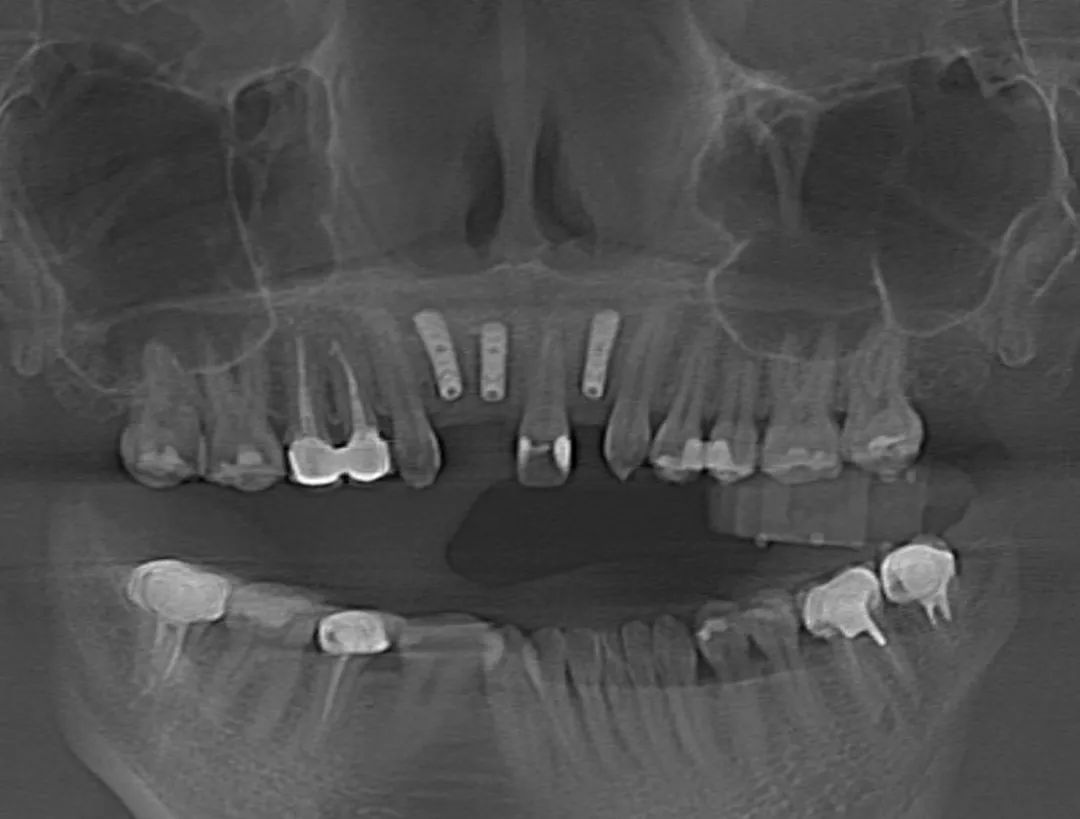

7月15日,瑞金醫(yī)院高益鳴主任團(tuán)隊(duì)實(shí)施了一例口腔手術(shù)機(jī)器人輔助下的上前牙美學(xué)區(qū)種植手術(shù),這是上海首例機(jī)器人輔助下的口腔種植手術(shù)。接受該手術(shù)的患者是一位年輕女性,她因意外事故導(dǎo)致前牙缺失,迫切希望能夠重拾笑容。高益鳴主任詳細(xì)了解她的病史及美學(xué)訴求,決定采用數(shù)字化技術(shù),為她訂制個(gè)性化種植方案。以往,前牙美學(xué)區(qū)的種植及修復(fù)只能依靠醫(yī)生的臨床經(jīng)驗(yàn),簡(jiǎn)單來(lái)講就是“手感”,但前牙美學(xué)區(qū)對(duì)術(shù)者技術(shù)要求極高,若是出現(xiàn)毫米級(jí)偏差,就無(wú)法達(dá)到理想的粉白美學(xué)(修復(fù)后的牙冠和牙齦美學(xué)指數(shù))效果,還會(huì)導(dǎo)致牙齦萎縮、種植體頸部暴露等諸多問(wèn)題。口腔手術(shù)機(jī)器人對(duì)此提出了新的解決方案,它可以通過(guò)術(shù)前可視化體外模擬,術(shù)中精準(zhǔn)定位、動(dòng)態(tài)導(dǎo)航、人機(jī)隨動(dòng)等功能,極大提升種植手術(shù)的精度和質(zhì)量。醫(yī)生可以借助口腔手術(shù)機(jī)器人,精準(zhǔn)完成口腔種植手術(shù),縮短手術(shù)時(shí)間,實(shí)現(xiàn)標(biāo)準(zhǔn)化種植。

術(shù)前,醫(yī)生將患者的影像學(xué)資料導(dǎo)入機(jī)器人系統(tǒng),進(jìn)行種植體植入全過(guò)程的體外可視化模擬,這樣手術(shù)團(tuán)隊(duì)能充分了解患者牙槽骨的骨量及解剖結(jié)構(gòu)走向,更詳盡地制訂手術(shù)方案。術(shù)中,高益鳴主任、李小曼醫(yī)生共同按既定方案,在機(jī)器人全自動(dòng)模式下,精準(zhǔn)標(biāo)定種植位點(diǎn)并逐級(jí)擴(kuò)孔備洞。而且,機(jī)械臂的減速區(qū)設(shè)定,讓機(jī)器人在入口時(shí)動(dòng)作不會(huì)過(guò)快,“溫柔”且“迅速”地有序按照指令進(jìn)行手術(shù)。手術(shù)過(guò)程相比傳統(tǒng)方式來(lái)說(shuō)縮短了近一半。如今,這位女士恢復(fù)良好。

其實(shí),手術(shù)過(guò)程中,患者頭部肯定會(huì)有輕微移動(dòng),而此次使用的“瑞醫(yī)博”口腔手術(shù)機(jī)器人(Remebot Dental Robot)是首款獲國(guó)家藥品監(jiān)督管理局(NMPA)認(rèn)證的口腔領(lǐng)域手術(shù)機(jī)器人,它具備的機(jī)器人隨動(dòng)功能,可以檢測(cè)患者位移,保證下鉆過(guò)程中軸向準(zhǔn)確性,加上虛擬影像空間和實(shí)際機(jī)器人空間的映射匹配,實(shí)現(xiàn)手術(shù)信息實(shí)時(shí)共享,確保預(yù)備窩洞及植入植體精確至毫米級(jí)水平,使手術(shù)精度控制在1°和0.5mm以內(nèi)。隨著數(shù)字化口腔的發(fā)展,口腔治療將會(huì)迎來(lái)更多可能,成為實(shí)現(xiàn)精準(zhǔn)、微創(chuàng)、智能化醫(yī)療的重要組成部分。